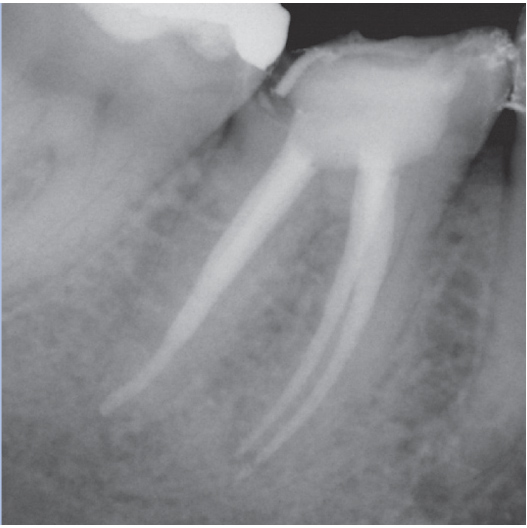

Before

Before Root Canal treatment